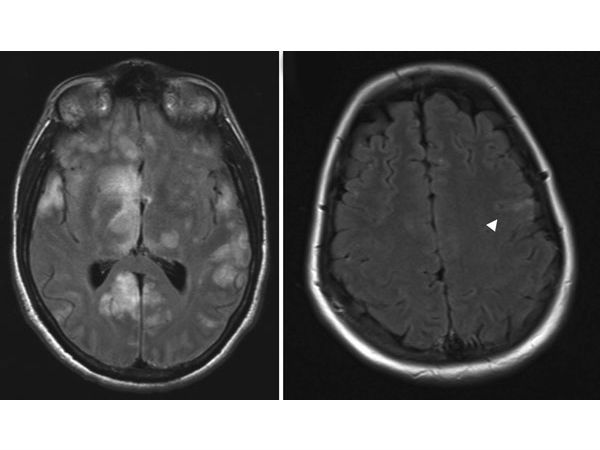

மூளை வீக்க நோய் பாதிப்பு குறித்து கண்டறியும் கருவிகள் கூட அங்குள்ள மருத்துவமனைகளில் இல்லாததால் பெரும்பாலானோர் இறக்க நேரிட்டுள்ளது.

உத்தரபிரதேச மாநிலத்தில் கடந்த 2009ம் ஆண்டு இந்த வகை மூளை வீக்க நோயால் 2,612 பேர் பாதிக்கப்பட்டு பல்வேறு மருத்துவமனைகளில் அவர்களில் 441 பேர் உயிரிழந்தனர் என்பது நினைவிருக்கலாம். இந்த கொடுமையான வியாதி ஏழை மக்களை தான் வெகுவாக தாக்குகிறது. இந்நோய்க்கு இதுவரை எவ்வித மருந்தும் கண்டுபிடிக்கப்படவில்லை என்பது குறிப்பிடத்தக்கது.